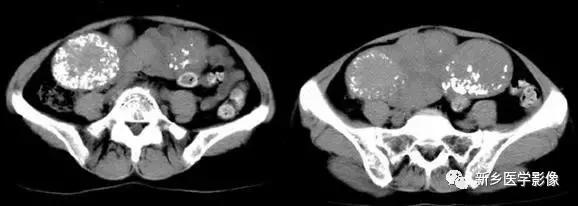

6、动脉钙化动脉瘤